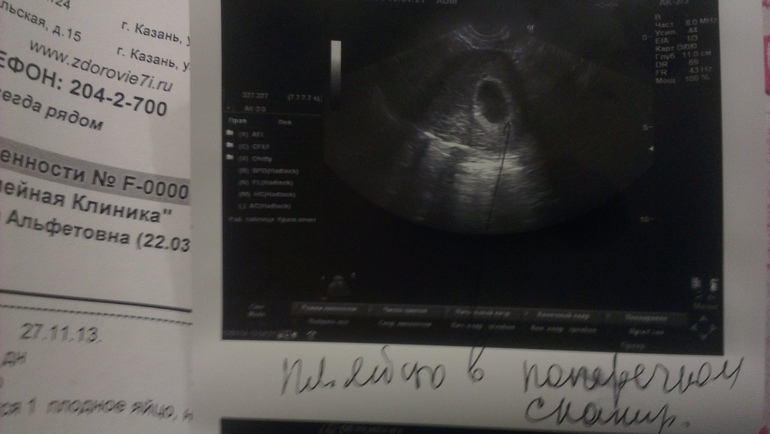

В полости матки визуализируется 1 плодное яйцо, несколько овальной формы при продольном сканировании

ВДПЯ 17мм

КТР 6мм

Сердцебиение +

Соответствует 4 нед 2 дня по дате зачатия